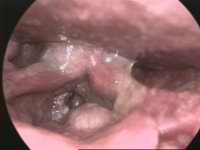

| Larynx cancer - endoscopic view | |

سرطان الحنجرة Laryngeal cancer، أو laryngeal carcinoma، هو في الغالب أحد سرطانات الخلية الحرشفية، تعكس أصلها من جـِلد الحنجرة.